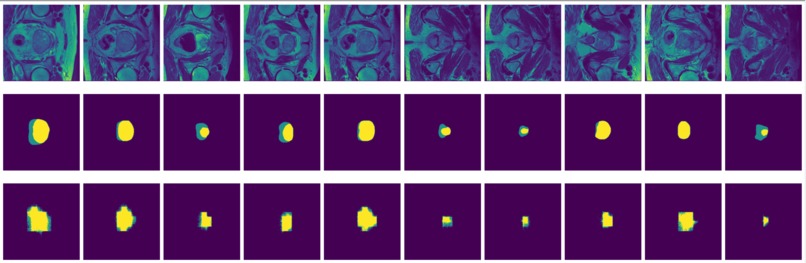

Figure 3: MRI slices (first and thrid rows) from one study with labels (second and fourth rows).

The prostate data set was acquired at Radboud University Medical Center, Nijmegen Medical Centre, Nijmegen, The Netherlands. It consists of 48 prostate multiparametric MRI (mpMRI) studies, 32 of them have corresponding region-of-interest (ROI) targets (background= 0, TZ= 1 and PZ= 2). Each study contains approximately 15 to 20 slices of MRI images, resulting in 602 images in total. Figure 3 shows the 20 slices from one study. The first and last few MRI slices contain little segmentation information. Therefore, to simplify the problem, we will discard the first and last 5 MRI slices from each study. We will use 10 studies (95 images) as the test set and the remaining 22 studies (187 images) as the training set.

FCN is outperformed by the two encoder-decoder models due to the thin deconvolutional layer as decoder and coarse output in the final deconvolutional layer. The dilated FCN managed to improve performance of FCN but is still outperformed by the encoder-decoder models. For the two encoder-decoder based models, U-Net outperforms DeConvNet in general. This is not surprising since U-Net is specifically designed for medical images and is supposed to achieve higher segmentation accuracy with fewer data. Moreover, randomly flipping input images seems to help improve performance for both of the models. Figure 8 and Figure 9 are the true (top) and predicted (bottom) segmentation of 10 test images from FCN and dilated FCN trained with data augmented by flipping and rotation. Figure 10 and Figure 11 are the true (top) and predicted (bottom) segmentation of 10 test images from DeConvNet and U-Net trained with data augmented by flipping and rotation. It can be seen that U-Net gives a smoother edge than FCN, dilated FCN and DeConvNet.